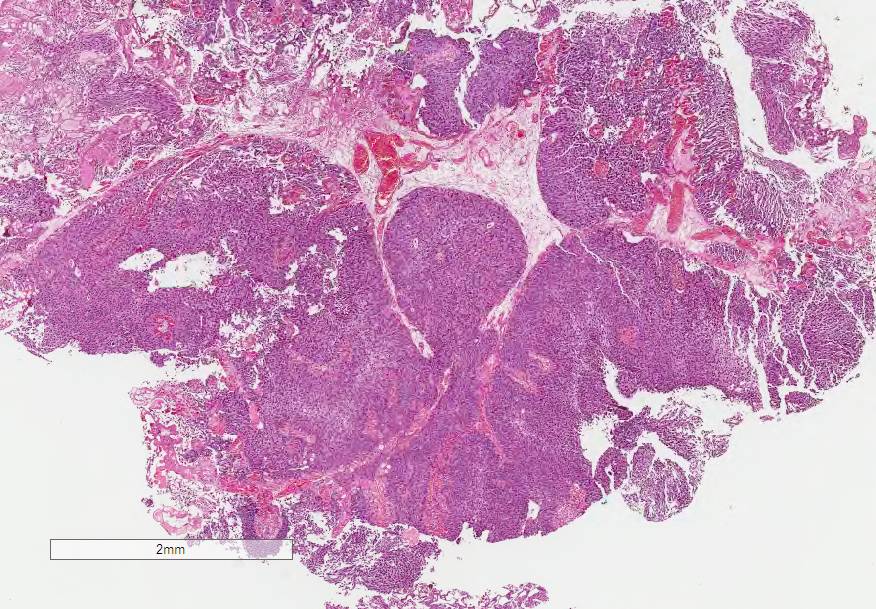

Bladder Papillary Lesions

Case ID: 646